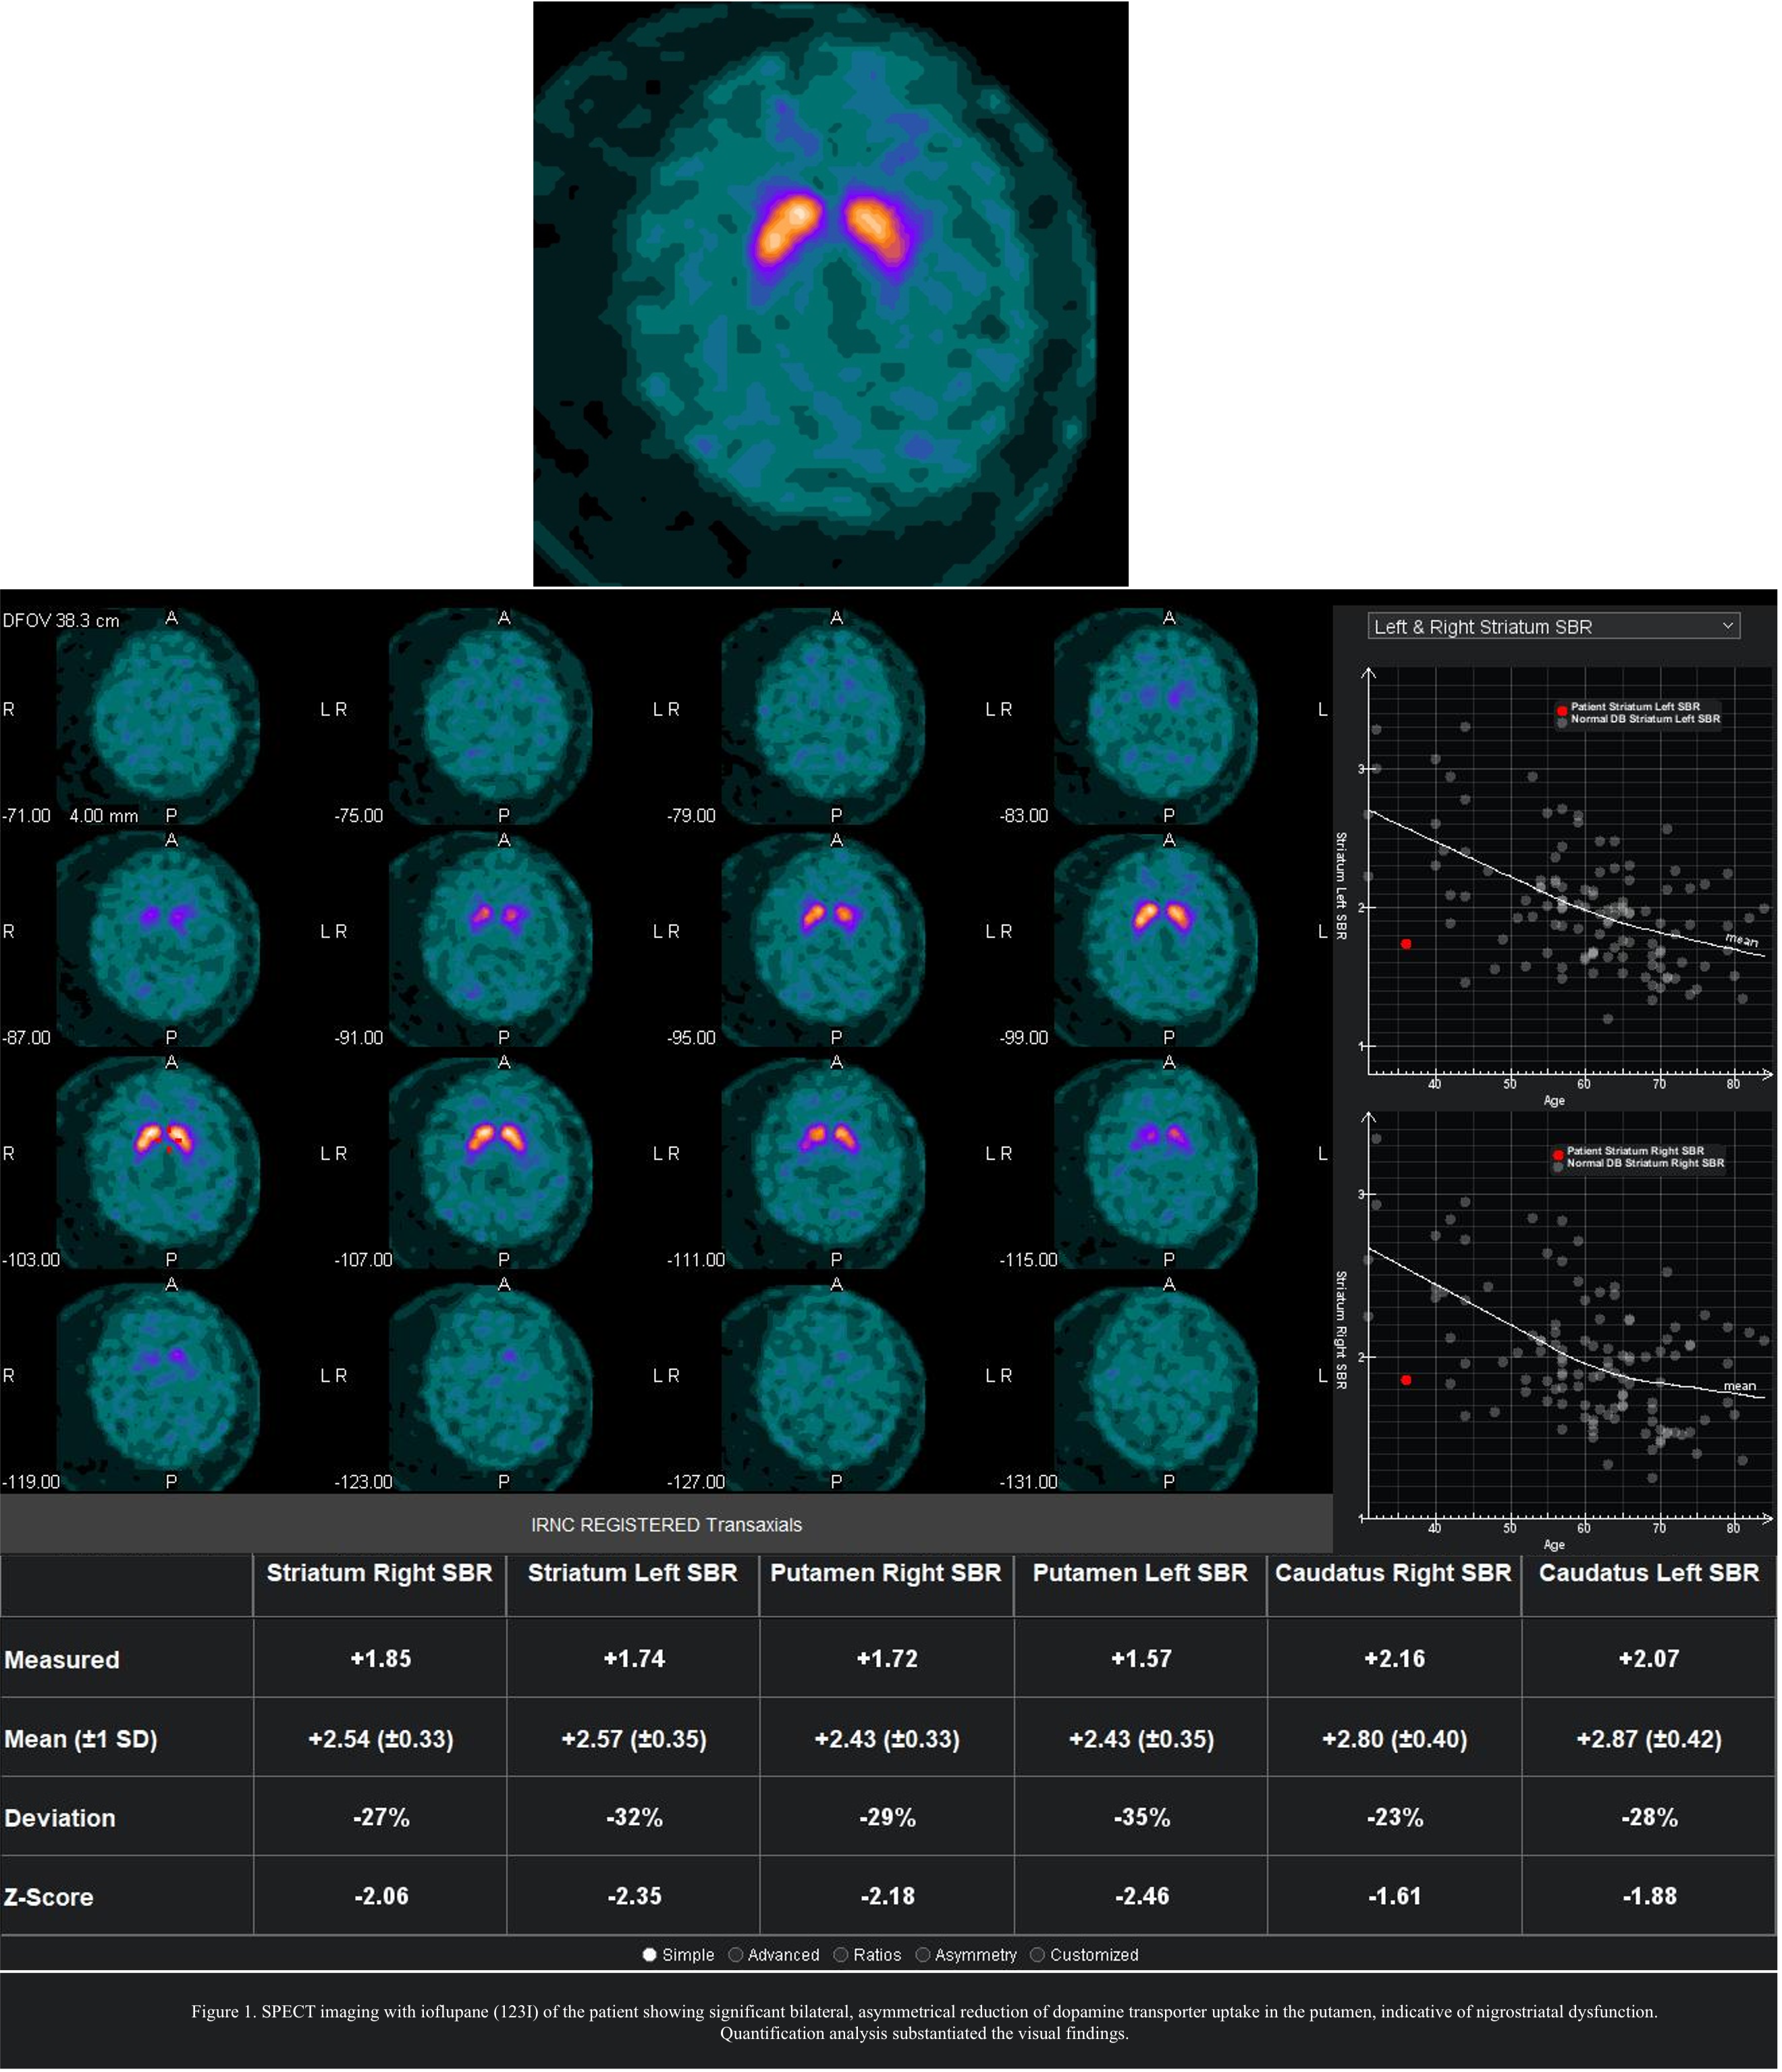

Results: We report the case of a 38-year-old woman with lifelong psychomotor delay, autistic features, intellectual disability and dysmorphic traits. She developed progressive parkinsonism at age 27 while receiving neuroleptic treatment. Clinical evaluation included neurological examination, SPECT imaging with ioflupane (123I), and genetic analysis, including next generation sequencing. Neurological findings revealed hypomimia, hypometric saccades, bradykinesia, rigidity, mild postural tremor, and pyramidal signs. Imaging [figure1] showed bilateral, asymmetrical dopaminergic deficit, suggesting a neurodegenerative component beyond the drug-induced parkinsonism. Whole-exome sequencing identified the heterozygous de novo c.581G>T (p.Gly194Val) variant in the KMT5B gene (NM_017635.4). The variant was absent from population databases, predicted to be deleterious, and classified as pathogenic per ACMG guidelines [5]. The patient’s parkinsonism remained stable despite neuroleptic reduction, and levodopa treatment was not initiated due to patient and family preference.

Conclusion: This case expands the phenotypic spectrum of KMT5B-related disorders, suggesting that parkinsonism may contribute to the motor features. While neuroleptic treatment could have contributed, imaging findings indicate a primary nigrostriatal dysfunction. Further studies are needed to determine the role of KMT5B in movement disorders.

Figure1